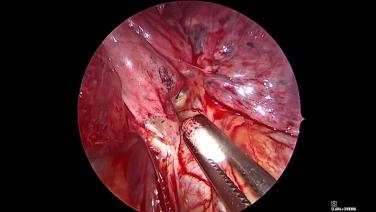

Thorascopic Lobectomy - Staple and Divide the Pulmonary Vein